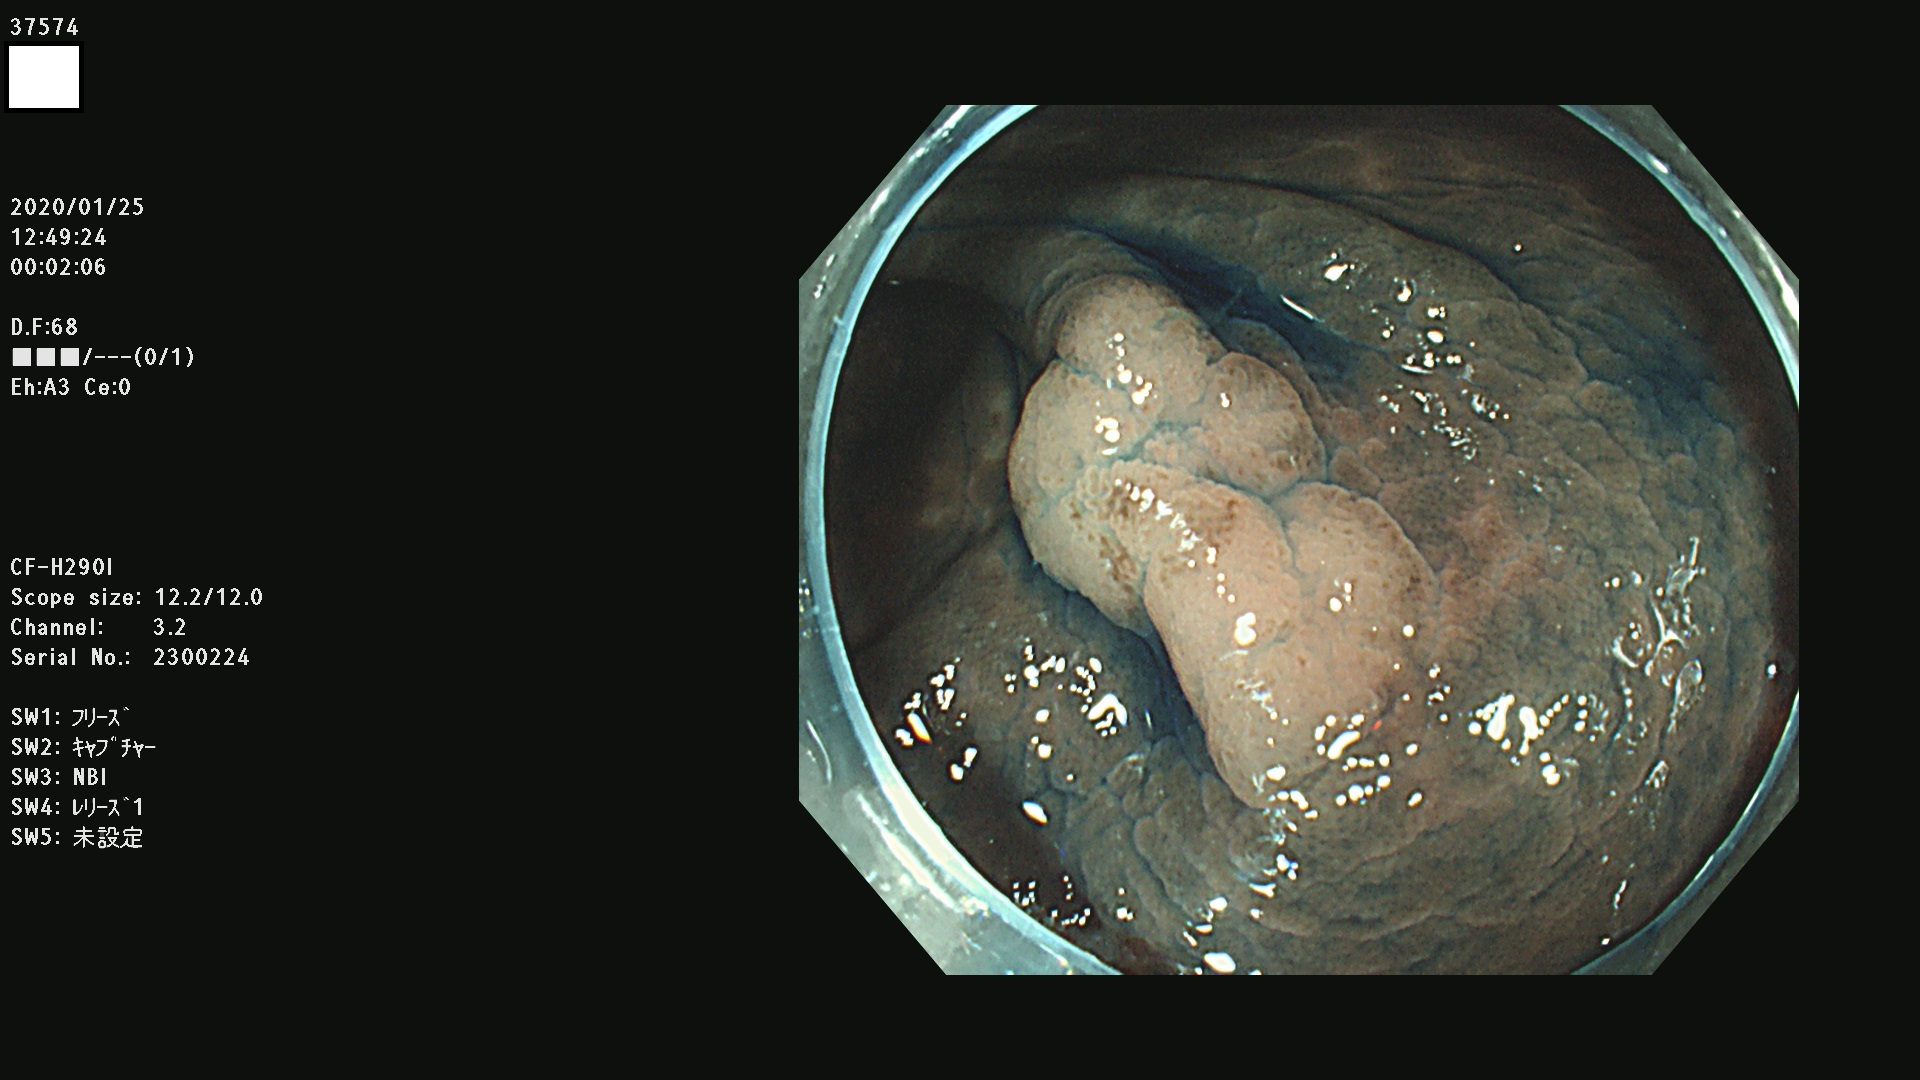

腺腫発見率 67 % (カルテ番号 37500〜37599の100名の方の検査結果で集計)大腸癌検診最新情報

以下のカルテ番号の方に腺腫(Adenoma,Group3〜5)が見つかりました(集計法)

37500 37502 37503 37505 37508 37509 37510 37511 37512 37513 37514 37517 37519 37520 37521 37525 37526(SSAPのみ) 37527 37528 37529 37531 37532 37533 37534 37536 37538(SSAPのみ) 37539 37541 37542 37543 37547 37548 37549(SSAPのみ) 37550 37552 37555 37556 37561 37562 37563(SSAPのみ) 37564 37565 37566 37567 37568 37570 37571 37572 37573 37574 37575(SSAPのみ) 37576 37577 37579 37580 37582 37583 37586(SSAPのみ) 37587 37588(SSAPのみ) 37590 37593(SSAPのみ) 37594 37596 37597(SSAPのみ) 37598 37599

発見困難で危険性の高い平坦型病変(上記100名より抽出) ![]()